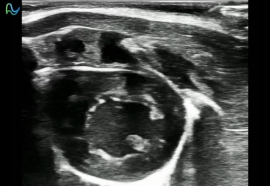

高频超声成像